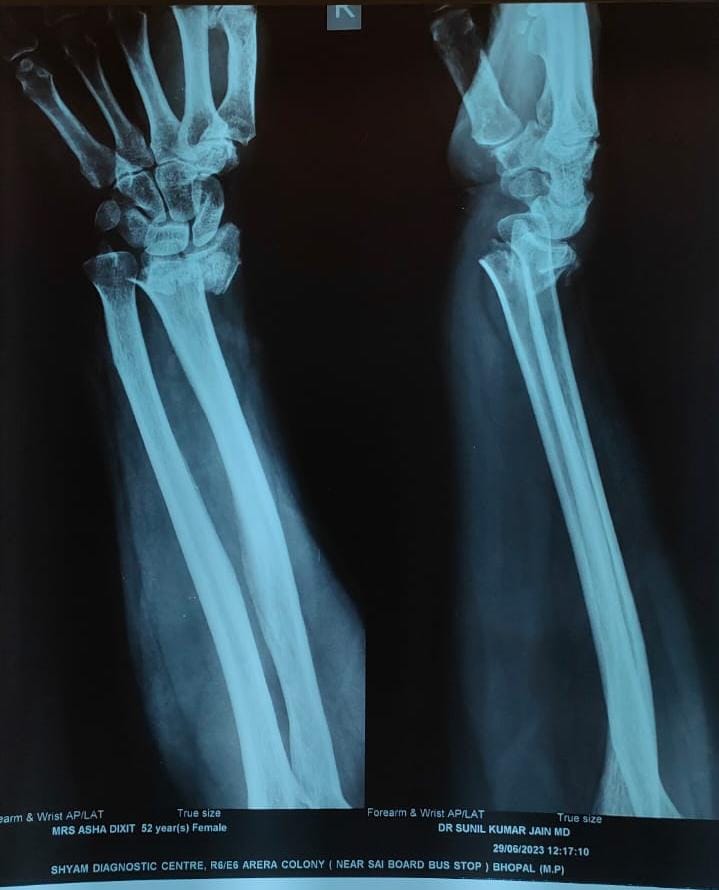

Welcome to the world of orthopedic excellence, where your health and well-being are our utmost priorities. Dr. Chetan Singh , an accomplished orthopedic surgeon, has been a dedicated practitioner in the vibrant city of Bhopal for the past 8 years. His unwavering commitment to providing exceptional orthopedic care has earned him a reputation as a trusted healthcare professional in the region. Meet Dr. Chetan Singh is a highly skilled orthopedic surgeon who has dedicated his career to improving the lives of patients suffering from orthopedic conditions. His educational journey began with the completion of an MBBS degree from Devi Ahilya Vishwa Vidyalaya, Indore, M.P. in 2015, where he laid the strong foundation for his medical expertise. Driven by his passion for orthopedics and a desire to offer the best care possible, Dr.Chetan Singh continued his educational journey. In 2019, he successfully achieved a Master of Surgery (MS) in Orthopedics from Madhya Pradesh Medical Science University, Jabalpur. This rigorous training equipped him with the knowledge, skills, and advanced techniques necessary to diagnose, treat, and manage a wide spectrum of orthopedic conditions.